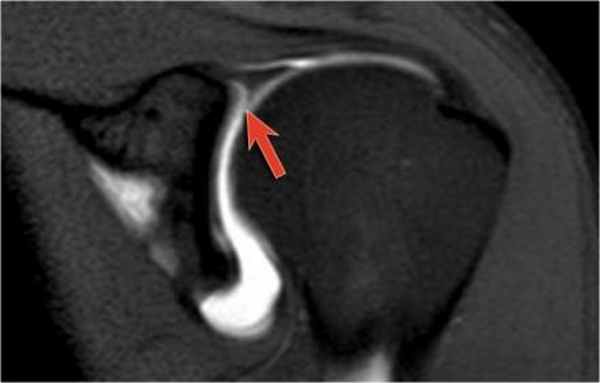

Вид в положении отведения и поворота плеча кнаружи (ABER)

Изображения в положении отведения и поворота плеча кнаружи получаются в аксиальной плоскости путем отклонения на 45 градусов от коротальной плоскости (см. иллюстрацию).

В этом положении область на 3-6 часов ориентирована перпендикулярно.

Обратите внимание на красную стрелку указывающую на небольшое повреждение Пертеса, которо не визуализировалось при стандартной аксиальной ориентации.

Повреждения суставной губы

Изображения в положении отведения и поворота плеча кнаружи является наилучшим для оценки передненижних отделов суставной губы в положении 3-6 часов, где локализуется большинство ее повреждений. В положении отведения и поворота плеча кнаружи суставно-плечевая связка растягивается напрягая передне-нижние отделы суставной губы, позволяя внутрисутавному контрасту попасть между повреждением губы и суставной впадиной.

Повреждение манжеты вращателей

Изображения в положении отведения и поворота плеча кнаружи так-же очень полезны для кизуализации как частичных так и полных повреждений манжеты вращателей. Отведение и поворот конечности кнаружи высвобождает натянутую манжету больше чем при обычных косых корональных изображений в положении приведения конечности. В результате небольшие частичные поврждения волокон суставной поверхности манжеты не прилегают ни к интактным пучкам, ни к головке плечевой кости, и внутрисуставной контраст улучшает визуализацию повреждений (3).